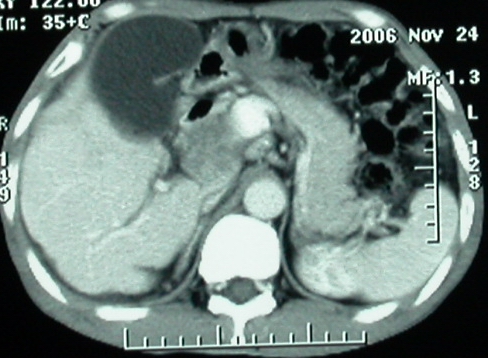

增强ct所见

1、胰头部占位:胰管轻度扩张(可疑双管征),主要考虑恶性肿瘤,胰头癌?十二指肠间质瘤?后腹膜肿瘤?

2、门静脉高压症,主要考虑胰头部肿块压迫或者浸润所致肝前性门静脉主干受压;肝功能尚可,脾脏不大,无脾亢;

3、胆囊积液、肝胆管积气、胆道扩张伴有胆道感染;

4、右肝后上段占位(考虑肝胆管结石伴肝组织萎缩?)

5、下腔静脉受压;

6、左半肝缺失,原因不明?

7、有无门静脉癌栓?

8、有无淋巴结肿大?